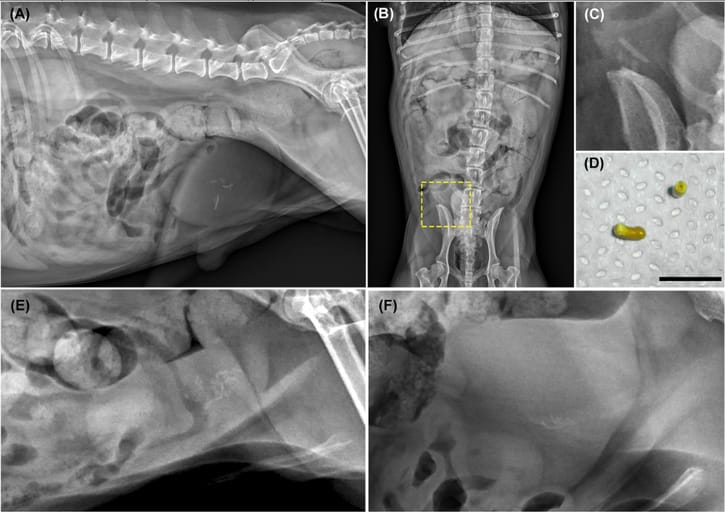

A, Right lateral abdominal compression study (digital radiography, Canon CXDI-50 IP, kVp 90, mAs 4.0) in a 10-year-old MN Poodle Mix. This study increases conspicuity of multifocal, linear, mineral opacities within the urinary bladder. Pin point mineral foci are also present within one of the kidneys. B, ventrodorsal projection (digital radiography, Canon CXDI-50 IP, kVp 90, mAs 4.0) of the abdomen of the same patient. Multifocal, linear, mineral opacities are within the urinary bladder, located to the right of mid line. C, Cropped image of multifocal cystic calculi on the previous ventrodorsal projection. D, Gross image of suture-related cystic calculi associated with the prior percutaneous cystolithotomy site of the patient in A, B, and C. The cystic calculus is cylindrical in shape with a hollow core. The black bar indicates 0.5 cm in length. E, A right lateral abdominal cropped image (digital radiography, Canon CXDI-50 IP, kVp 90 mAs 4.0) in a 7-year-old MN Pomeranian with round, pin point as well as linear mineral opacities within the urinary bladder. F, A right lateral abdominal cropped image (digital radiography, Canon CXDI-50 IP, kVp 90, mAs 4.0) in an 8-year-old MN Maltese Mix with multifocal linear mineral opacities within the urinary bladder [Color figure can be viewed at wileyonlinelibrary.com]

Seven cases were identified, involving six dogs (one dog presented twice). Affected dogs were all neutered males, small breed (3.2–10.7 kg), and middle-aged (mean 9.4 years). Radiographic findings showed multiple linear, mineral-dense calculi located centrally within the bladder. One dog exhibited both round and linear calculi. Gross examination confirmed a hollow core in all cases. Calculi were composed of calcium oxalate. Prior cystotomies had used monofilament absorbable sutures (polydioxanone or poliglecaprone 25), though two cases had unknown suture material. Recurrence time ranged from 3 months to 2 years post-surgery.